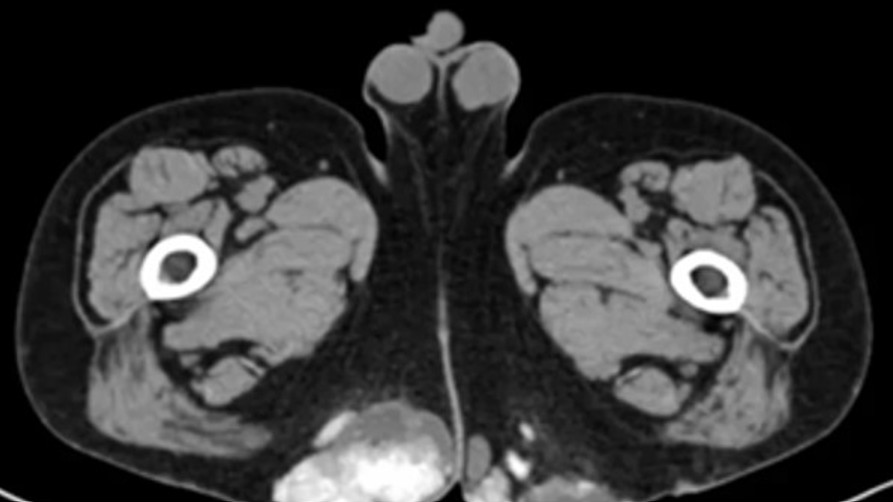

Figure 2 for case Gout

Figure 2

Subcutaneous soft tissue mass in the buttocks with lobulated borders and areas of internal high density or apparent calcification.

Gout